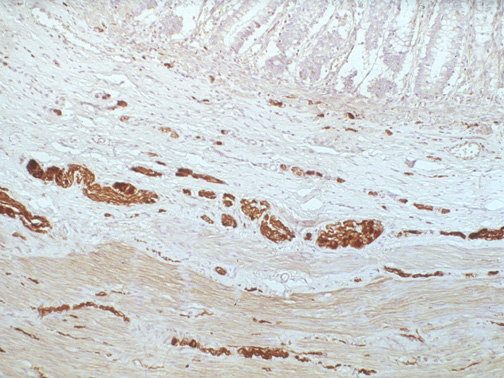

The submucosal plexuses with ganglia are seen here in the colon with immunohistochemical staining for S-100, a marker of neuronal differentiation. This stain also highlights small nerves .